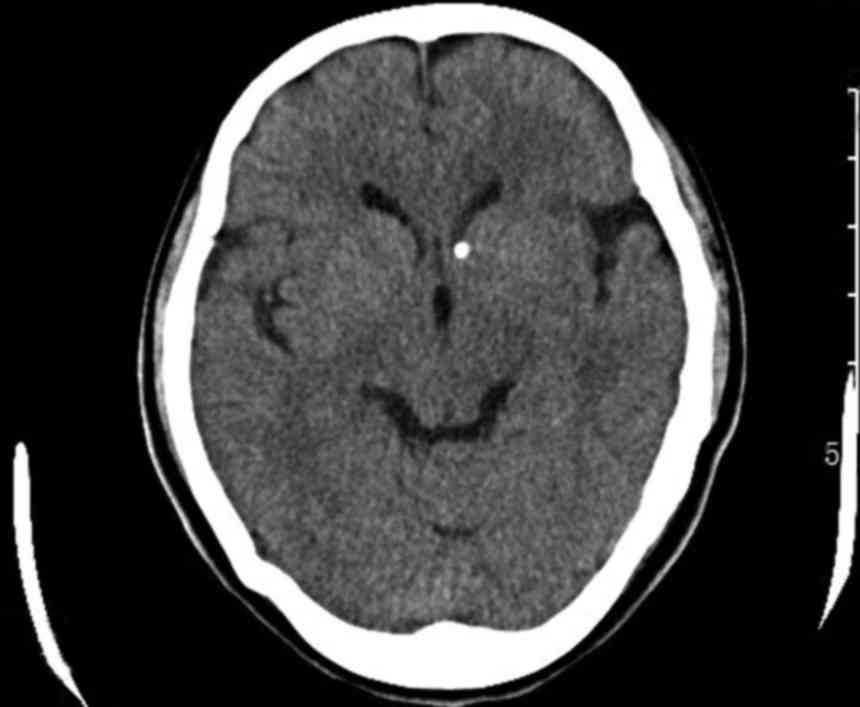

Tuberous sclerosis-associated renal angiomyolipoma: A report of two cases and review of the literature

In the general population, tuberous sclerosis‑associated renal angiomyolipoma (RAML) is a rare benign hamartoma with potentially life‑threatening complications and a poor prognosis. The two patients reported in the present study, who were diagnosed with bilateral RAML and spontaneous rupture of the RAML with tuberous sclerosis, presented with flank pain, abdominal pain, hemorrhage, hematuria and multiple lesions. The two cases are representative examples of the disease, and highlight the importance of determining the risk of acute hemorrhage in the early stages, and the significance of timely and proper treatment.

Figure 1

Figure 2

Figure 3

Figure 4

Figure 5